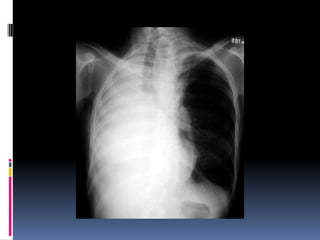

Underpenetrated Film Hemi diaphragmsare obscured Pulmonary markings more prominent than they actually

Over penetrated Film Lung fields darker than normal—may obscure subtle pathologies • See spine well beyond the diaphragms • Inadequate lung detail